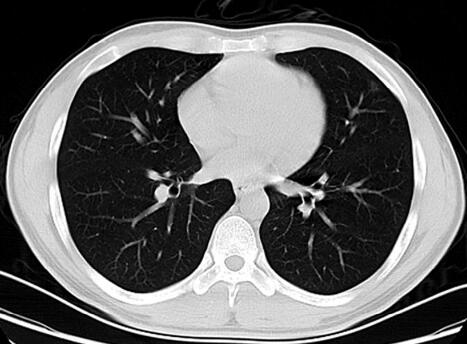

6.胸部CT:左肺上叶下舌段可见斑片状磨玻璃影(图1),肝胆脾胰彩超:脾大(脾肋间厚约4.5cm,肋间长15.4cm),胆囊壁毛糙。

图1

重要的检查结果有五项:①末梢血淋巴细胞百分比增高;②胸部CT示左肺上叶磨玻璃影;③肝功能异常,以酶系升高为主;④脾大;⑤肺炎支原体抗体IgM 1∶160阳性。结合患者的病史和体格检查结果,进一步支持感染性疾病——社区获得性肺炎(CAP)的诊断,目前病原学考虑肺炎支原体感染。

但有些疑问需要进一步解决:①患者诊断社区获得性肺炎,致病菌为肺炎支原体,院外应用“罗红霉素、左氧氟沙星”,这些都是针对不典型致病菌的药物,但患者仍有发热,原因何在?病原体耐药?治疗不规范?合并其他疾病?混合感染?②淋巴细胞比例升高,单纯用支原体感染解释不通,是否存在混合感染?或药物性淋巴细胞升高?③患者肝功能异常、脾脏增大原因不清,是肺炎支原体感染的肺外表现?药物性?感染性?血液系统疾病?④患者胸部影像学改变与发热程度似乎不符,如此小斑片影能否引起持久发热?或院外抗感染治疗有效?